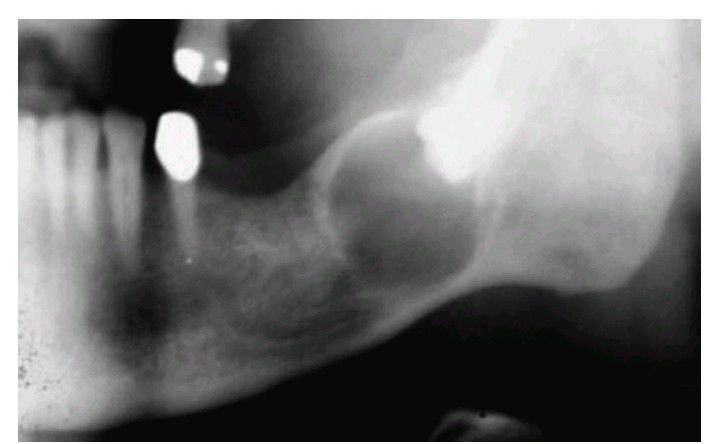

Ameloblastoma associated with the crown of an impacted third molar. (Courtesy Dr. Frances Gordy.)